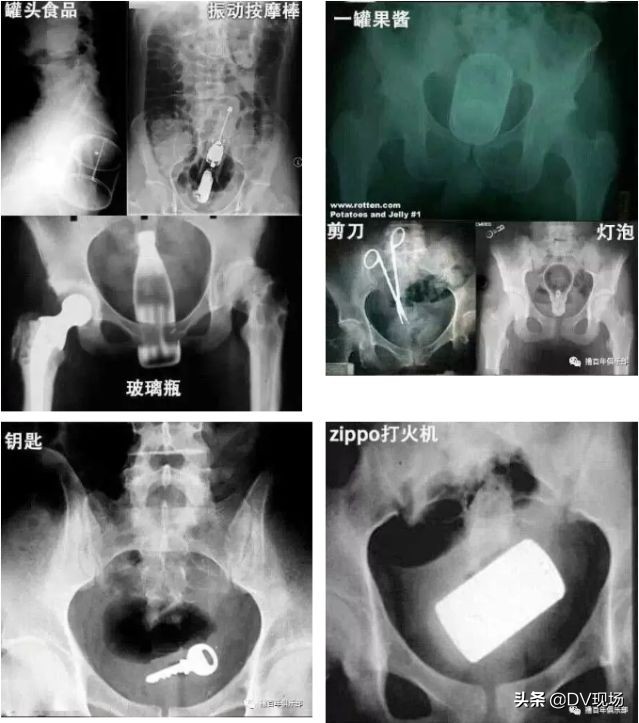

不过大家还别说

异物进体内,只有你想不到的

没有它做不到的!

玻璃瓶、剪刀

灯泡、钥匙、打火机甚至果酱

这些存在直肠的异物

也太恐怖了吧

对于直肠异物,不能及时排除或自行拿出,以及在取出过程中出现便血、腹痛、腹胀、肛门肿痛、发热等情况,需要及时就医,以免延误病情,造成严重后果!因此,千万不要讳疾忌医!